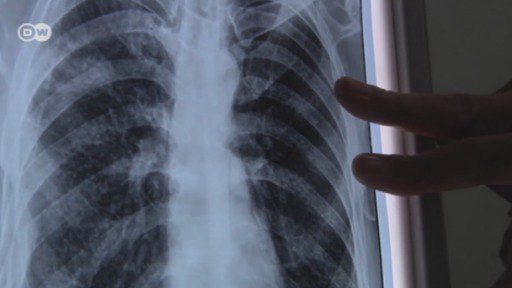

One of the main millennial goals was to control the spread of diseases like malaria, HIV and tuberculosis. But a medication-resistant tuberculosis bacteria is becoming more and more prevalent in India. Mumbai's slums are breeding ground for tuberculosis because hygienic conditions are poor and people are malnourished.

The fight against the illness requires pharmaceutical innovations and better urban planning. Mumbai's slums are breeding ground for tuberculosis because hygienic conditions are poor and people are malnourished.